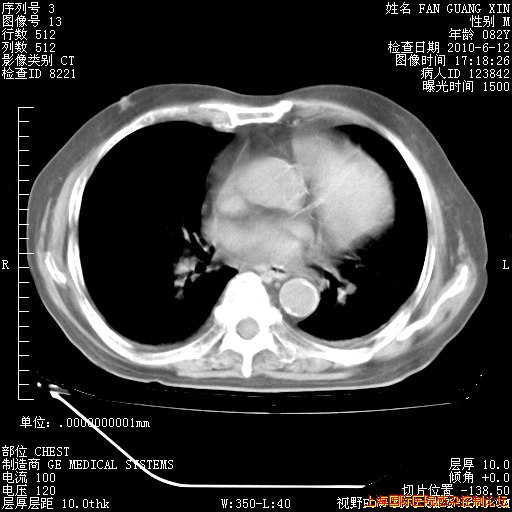

6月12日纵膈窗

6月10日改甲强龙80mg qd ,在南京年会期间体温不稳,18日有一次寒战后体温达39度。19日开始用甲强龙60mg bid ,加量后第二天就不发热。本打算在两周后即7月3日减量,但是7月2日洗澡受凉、发热、咳嗽、鼻音,口服复方大青叶片,甲强龙120mg用到9日(整整20天)。

自昨天起甲强龙改为80mg qd。

在抗结核治疗2周后一般情况逐渐好转。

整整相隔30天的肺部CT好像有所好转啊。甲强龙减量第3天,需要观察体温。

海管,自昨日你和我通完话后,不知您岳父消化道症状有无缓解?体温怎样?阅读7.12日胸部ct,个人认为目前激素治疗是有效的,甲强龙减量是适宜的。因在抗痨治疗,需密切观察肝功、肾功能和血常规。不过,老年、长期住院和大量使用激素,很担心菌群失调发生